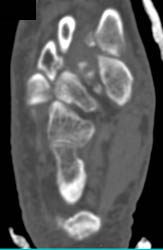

Diagnosis

Abscess Around Vessels